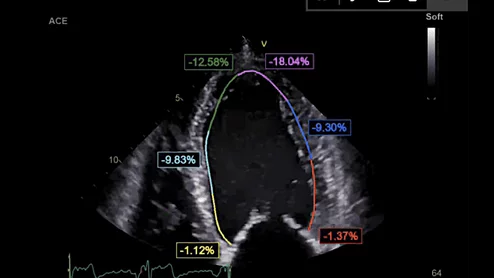

American Society of Echocardiography (ASE) President David H. Wiener, MD, FACC, FAHA, FASE, director of clinical operations at the Jefferson Heart Institute, and a clinical professor of medicine at Thomas Jefferson University, explains the growing number of multimodality cardiac imaging experts and how imaging societies need to change to meet their needs.

ASE President David Wiener detailed some of the many ways imaging societies need to adapt now that so many imagers are specializing in multiple modalities. It may be time to change how annual conferences are scheduled, for example, so that the costs of travel are easier to manage.